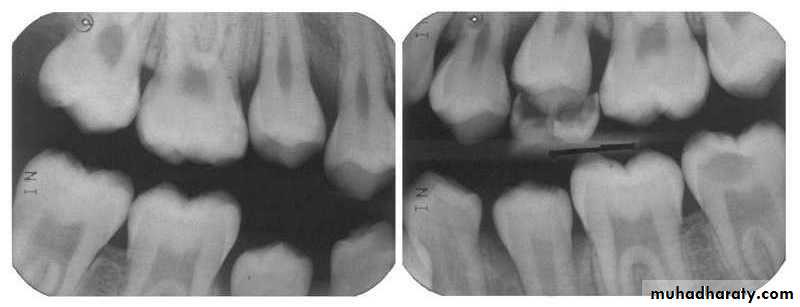

(A) Improper vertical angulation (excessive) obliterates viewing this proximal surface carious lesion. (B) Proper vertical angulation shows interproximal cariesDental Caries

Horizontal angulation. (1) Improper horizontal angulation prevents viewing interproximal caries. (2) Improved horizontal angulation, but caries difficult to view. (3) Proper horizontal angulation shows interproximal caries